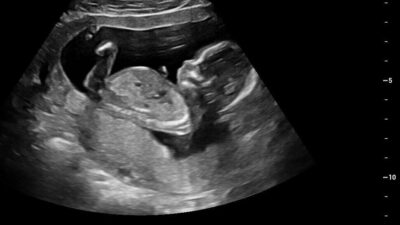

A regular (2D) ultrasound is like peering at just one slice of that loaf. You get a detailed, flat, black-and-white image of that specific cross-section. Doctors are like bread connoisseurs, expertly interpreting these “slices” to ensure everything is just right.

What You See:

With a regular (2D) ultrasound, you’re looking at a flat, black-and-white cross-section. But with a 3D ultrasound, you get a golden-toned, three-dimensional image that brings your baby to life!

The Picture:

A regular ultrasound looks like a collection of shadows and shapes (which experts can read like a book). In contrast, a 3D ultrasound resembles a detailed, sculpted model of your baby, showcasing all those adorable details!